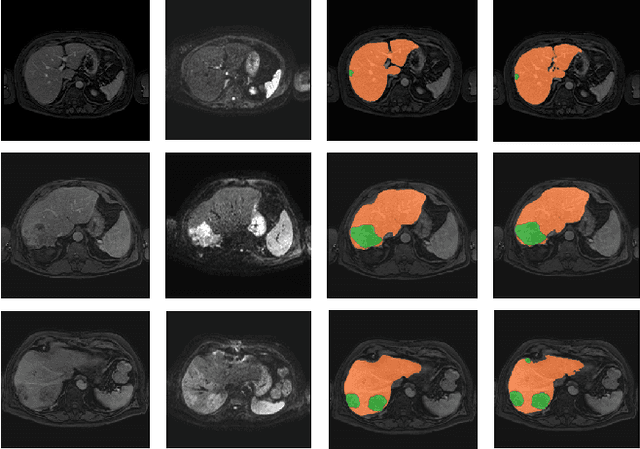

Abstract:Primary tumors have a high likelihood of developing metastases in the liver and early detection of these metastases is crucial for patient outcome. We propose a method based on convolutional neural networks (CNN) to detect liver metastases. First, the liver was automatically segmented using the six phases of abdominal dynamic contrast enhanced (DCE) MR images. Next, DCE-MR and diffusion weighted (DW) MR images are used for metastases detection within the liver mask. The liver segmentations have a median Dice similarity coefficient of 0.95 compared with manual annotations. The metastases detection method has a sensitivity of 99.8% with a median of 2 false positives per image. The combination of the two MR sequences in a dual pathway network is proven valuable for the detection of liver metastases. In conclusion, a high quality liver segmentation can be obtained in which we can successfully detect liver metastases.